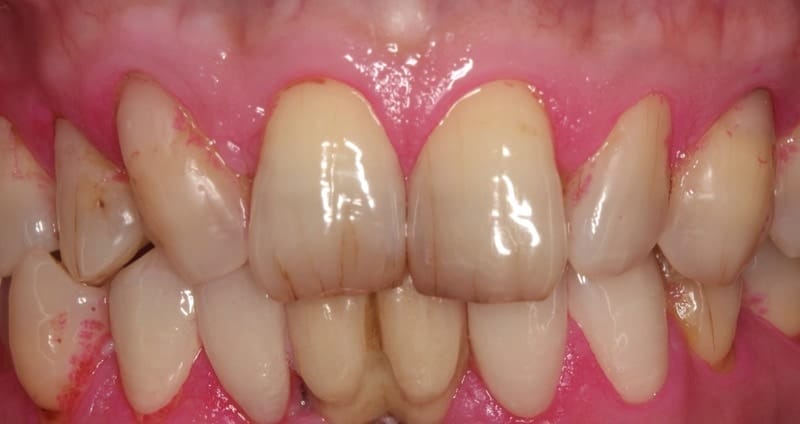

圖示:上顎全瓷修復治療前近照,先天缺右上側門牙,讓犬齒看起來較尖

上顎前牙區,Mr.Hsieh是先天少了一顆右上側門牙,原來的空間因為時間久遠而關閉。右上犬齒佔據了原來側門牙的位置,形態上看起來比較尖,對稱性就會比較差。

我們的治療計畫是利用全瓷貼片能夠改變形態以及改變牙齒排列的優勢,讓犬齒取代原本的側門牙,同時把前牙空間分配,這樣能夠讓他的微笑曲線和牙齒能夠更加協調。